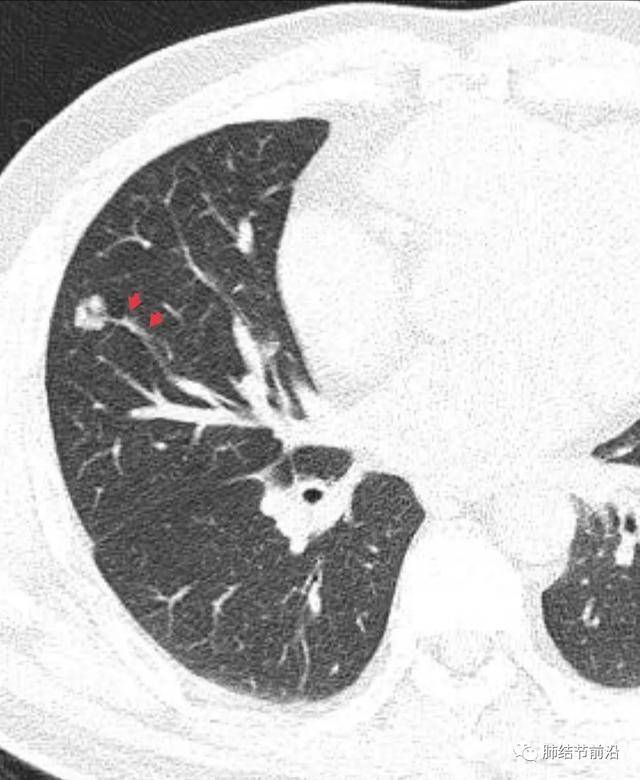

肺結(jié)節(jié)的診斷

診斷肺結(jié)節(jié)主要依賴于醫(yī)學(xué)影像技術(shù),如X光、CT等,醫(yī)生會(huì)根據(jù)患者的病史、體征和影像學(xué)表現(xiàn)進(jìn)行綜合判斷,對(duì)于疑似惡性的結(jié)節(jié),可能需要進(jìn)行進(jìn)一步的檢查,如活檢等。